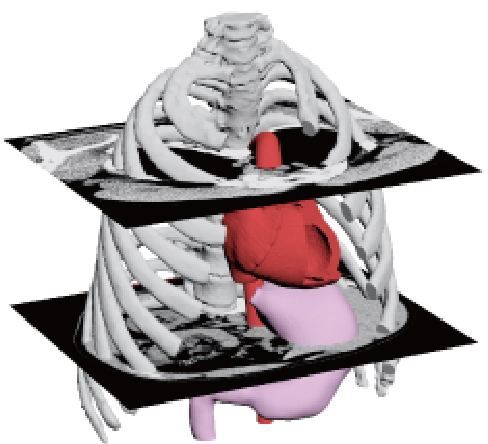

From CT imaging to 3D printer output

- Reads DICOM data obtained from CT imaging into mimics

- Eliminates noise (artifacts) generated by metal and other materials

-

3D data is converted to images or data to see if the region of interest is

We will confirm with the customer that the area of interest has been reproduced.

The customer will be asked to confirm that the area of interest is reproduced in the image or data.If the STL output is available directly from the medical workstation, the above process is eliminated.